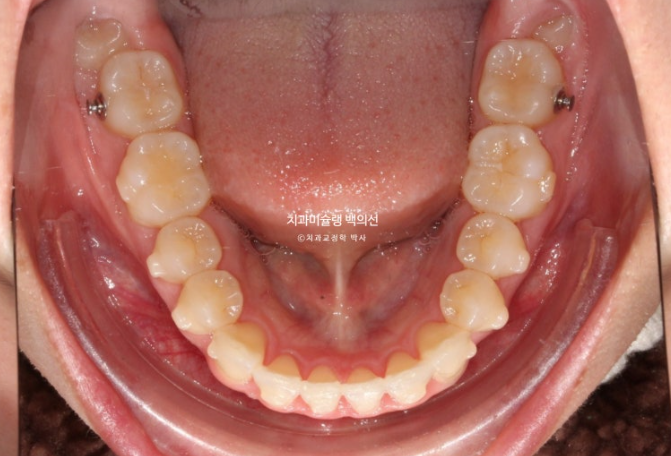

앞니가 삐뚠 부분이 있습니다.

환자분은 발치교정은 원치 않았기에 치료계획은 사랑니 발치하고 사랑니 공간으로 어금니를 밀어 앞니를 가지런히 펴고 뒤로 넣는 계획입니다.

어금니 후방이동에 필요한 교정용 나사를 심고 진행합니다.